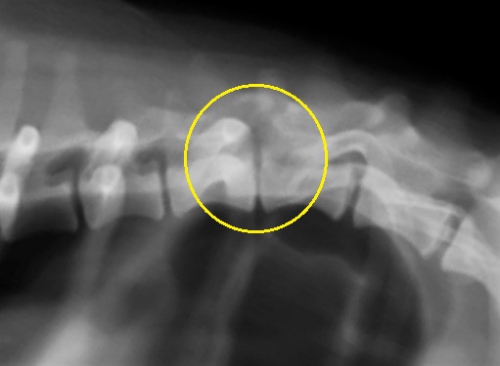

レントゲン検査が最初に必要な検査ですが、この検査では椎間板ヘルニアの確定診断にはなりません。「ヘルニア」はレントゲンに映り難く診断精度が高くないために、体の各部の刺激に対する反応を評価しながら系統的に行う、神経学的検査により神経的な異常部位とレントゲン検査の結果と合わせて病変の場所を予想します。下の写真ではヘルニアがある部位にはレントゲンでの異常が見られません。

MRIでの椎間板ヘルニアが下の写真です。黄色丸の中にヘルニアを起こしている圧迫物質が「黒い影」として映っています。左写真がサジタル像(側面像)です。上の写真と全く同じ部位を撮影したものが下の画像です。